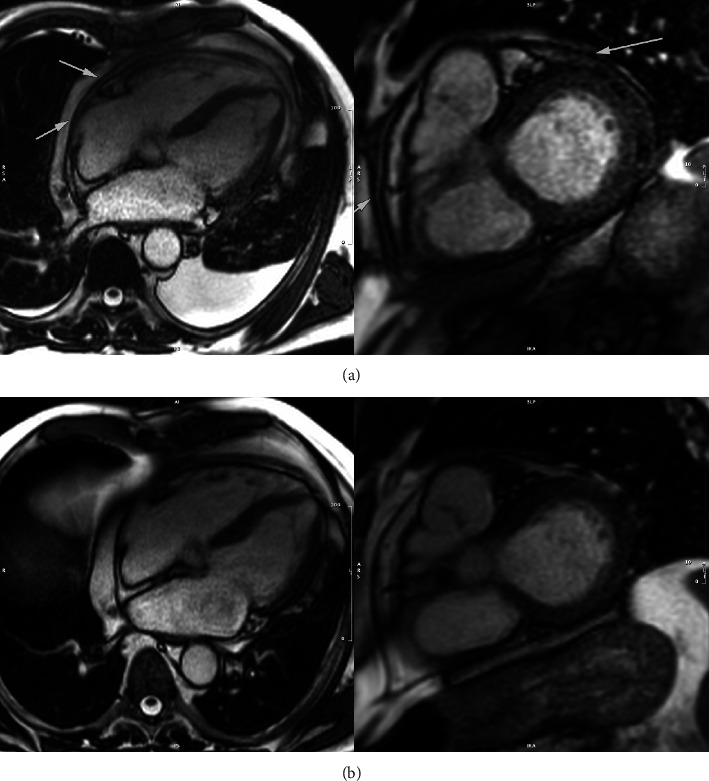

Introduction: The introduction of Bruton's tyrosine kinase (BTK) inhibitors significantly improved the management of chronic lymphocytic leukemia (CLL). However, BTK carry the risk of cardiotoxicity, which is not only limited to atrial fibrillation. Case Reports. We report three cases of patients on BTK inhibitors who developed acute pericarditis and cardiac tamponade. We report the first patient who developed this complication on treatment with zanubrutinib. This patient's treatment was changed to zanubrutinib due to atrial fibrillation. Shortly after cardioversion, he developed cardiac tamponade and shock. He underwent pericardiocentesis, received treatment for acute pericarditis with steroids and colchicine, and made a full recovery. We also report two further cases, both involving patients treated with ibrutinib. These patients also developed acute pericarditis and cardiac tamponade and required pericardiocentesis. All three patients discontinued BTK therapy following the events.

Conclusions: These three cases highlight the rare but potentially life-threatening risk of cardiac tamponade which can occur even with newer generations of BTK inhibitors. Haemato-oncologists should remain vigilant in patients who report dyspnea or who show sinus tachycardia on routine electrocardiography. Even in the absence of classical clinical signs of tamponade, patients require urgent evaluation with echocardiography and potentially emergency pericardiocentesis.